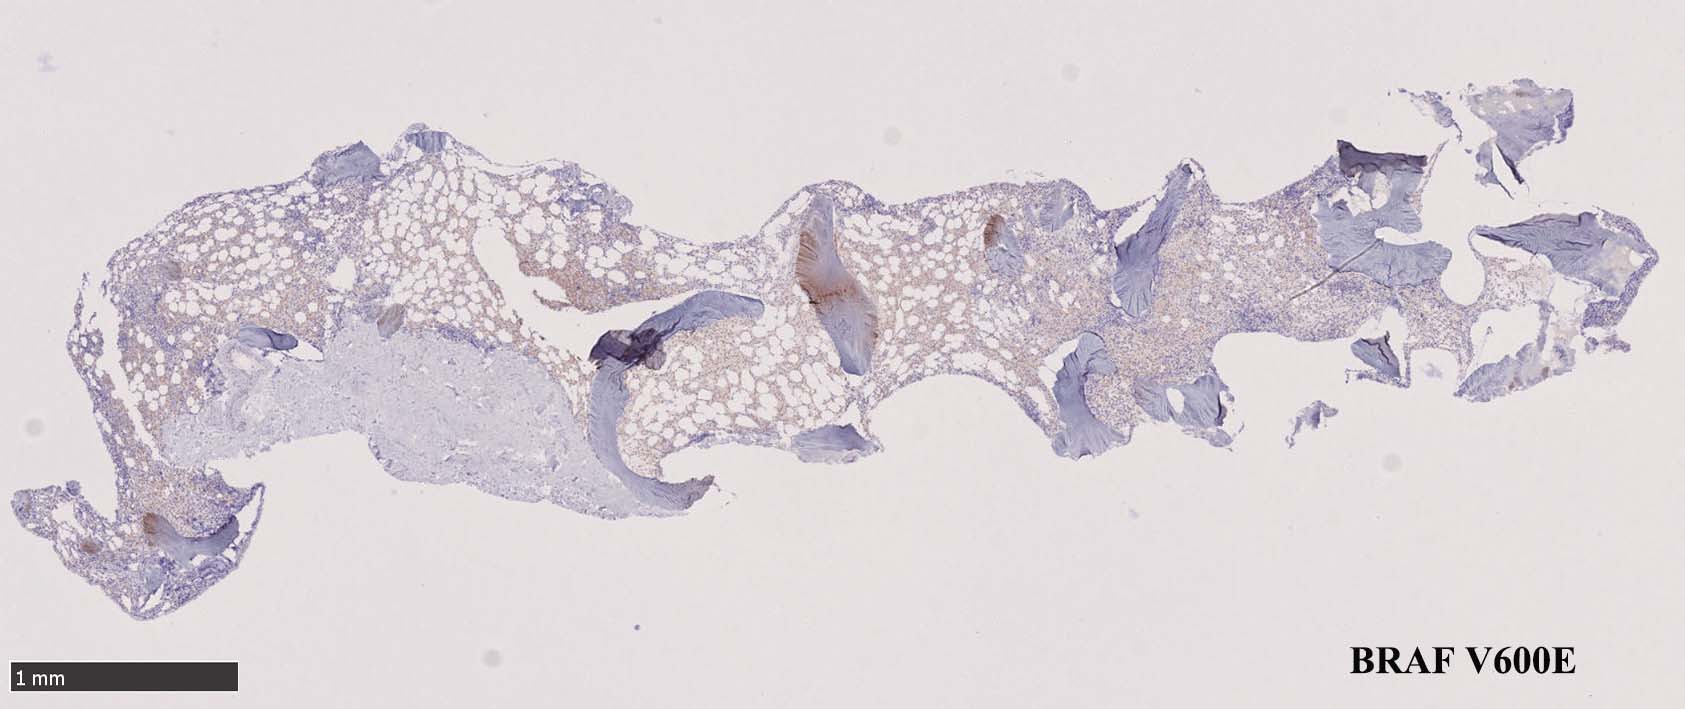

BRAF V600E変異タンパクの免疫染色(山梨医大 大石先生に染色していただきました. ベンタナ, Optiview)

Pathological Diagnosis: Hariy cell leukaemia